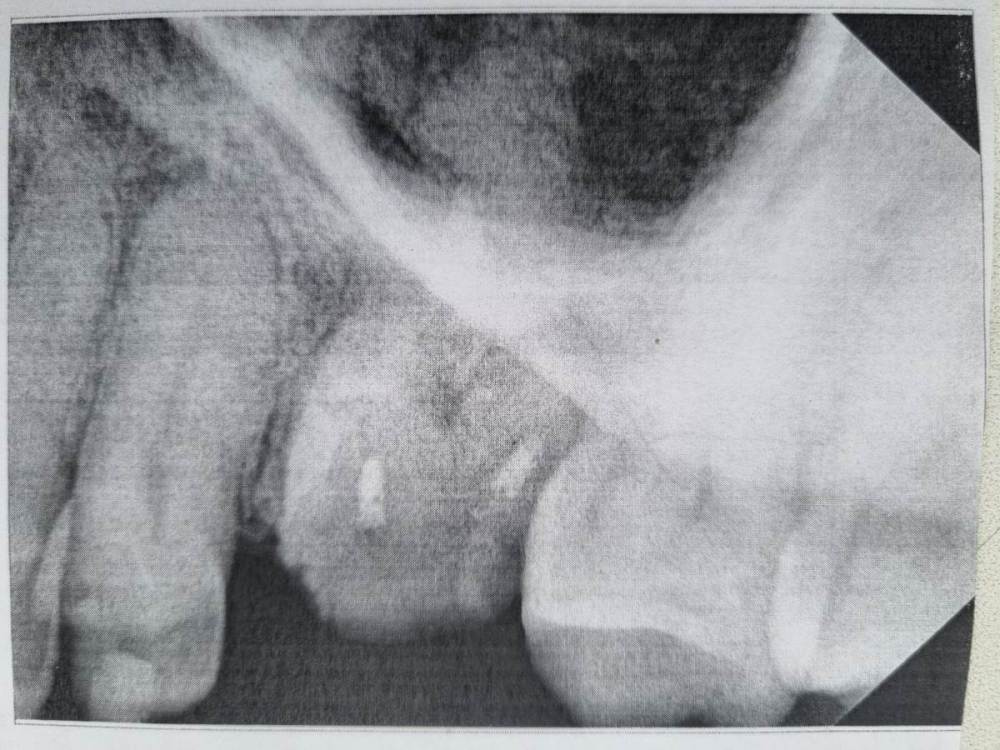

Окончательно упала коронка  металлопласт с 26го зуб, которая простояла 28 лет. 10 лет  назад она уже падала и ее восстановили на штифте. Хочу поставить новую коронку, либо на штифте, а лучше на культевой вкладке. Наверное, надо перецементировать каналы. Что стоит делать с зубом по фото и во сколько можно уложиться?